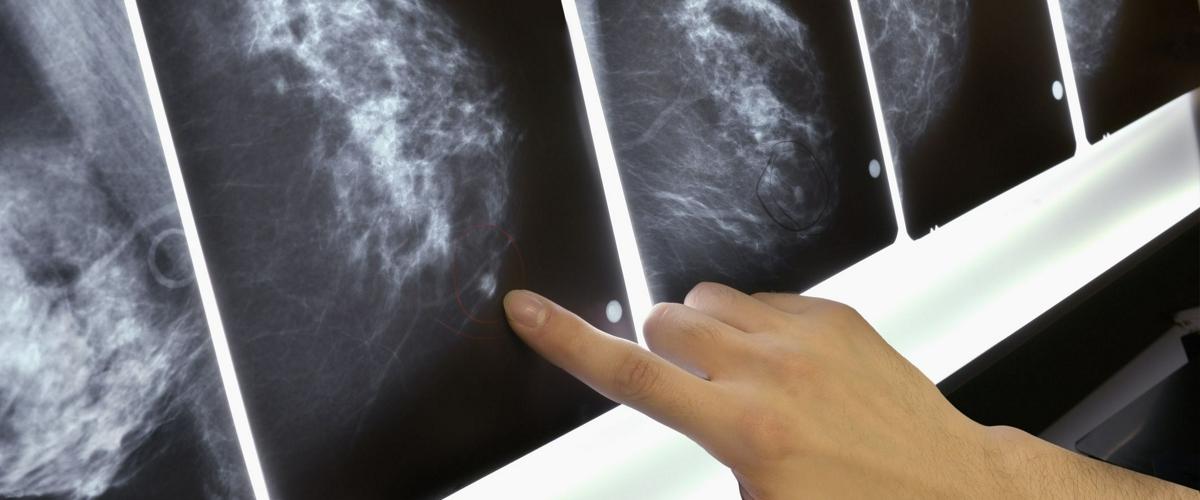

В ходе работы над ИИ исследователи проанализировали снимки 60 000 женщин, у некоторых из которых после обследования развился рак груди. Благодаря этим данным удалось выявить тонкие различия в структуре ткани — первые признаки будущей болезни.

У нового алгоритма не выявлено различий в эффективности для пациенток с разным цветом кожи. Авторы исследования связывают это с тем, что набор данных, использовавшийся для обучения нейросети, включал достаточное число разнообразных снимков.